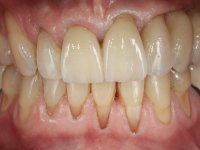

A temporary acrylic bridge made in the laboratory with 7 elements was made, with teeth 11,21, 25 and 26 as pillars. The old bridge was removed and tooth 24 was extracted. The provisional bridge after relining was cemented in the mouth. Two implants were placed in the teeth 22 and 24 and 3 months after this intervention an impression was made to make a temporary bridge screwed over the implants and cemented to the teeth. The bridge was placed in the mouth and teeth 25 and 26 were extracted. 3 months later, surgery was performed to fill the maxillary sinus and 6 months later the implant was placed in the location of tooth 26. After osseointegration of this implant, the final impression was made for the final work. The bridge over the implants was permanently screwed on and the bridge over the teeth was cemented with resin-reinforced glass ionomer cement.